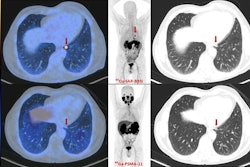

An image showing potentially different sites of PET radiotracer uptake by prostate cancer tumors between U.S. approved Ga-68 PSMA-PET and experimental Ga-68 RM2. Image courtesy of Heying Duan, MD, Stanford University.

Several prostate-specific membrane antigen (PSMA) PET radiotracers for detecting BCR prostate cancer have been approved in the U.S., such as Ga-68 PSMA-11 and F-18 DCFPyl (Pylarify, Lantheus Medical Imaging) and are included in National Comprehensive Cancer Network guidelines, Duan explained. Yet up to 10% of cases do not express PSMA, she noted.

Thus, Duan and colleagues developed a tracer called Ga-68 RM2, which targets other receptors overexpressed in prostate cancer – namely, gastrin-releasing peptide receptors (GRPRs). Previous studies by the team found the tracer is effective at revealing this activity on PET.

Ultimately, given high intratumor heterogeneity in prostate cancer, targeting a single tumor characteristic might not be sufficient to reflect the full extent of disease, Duan noted. Therefore, Ga-68 RM2-PET should be considered in addition to PSMA-PET in BCR prostate cancer patients to aid in disease detection and management decision, she suggested.